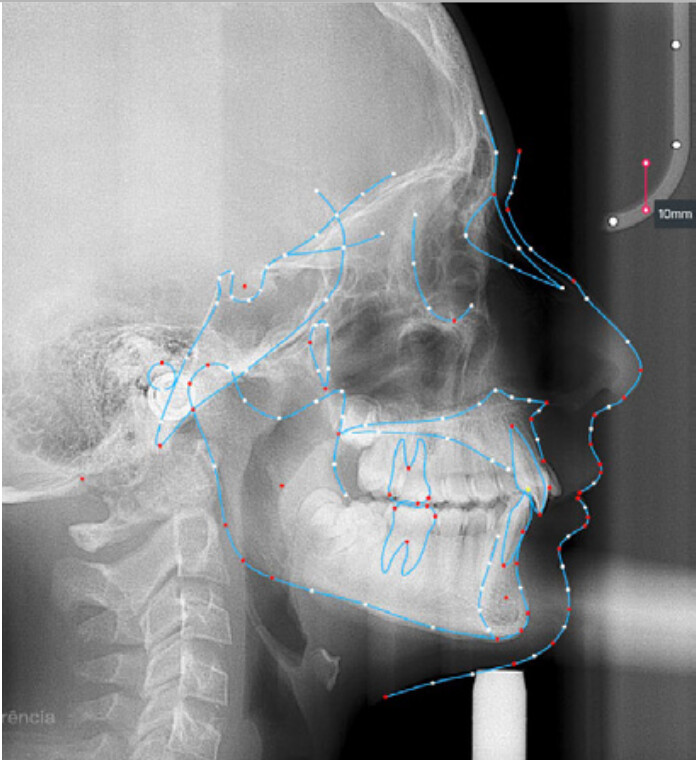

A 13-year-old male patient presented with a deep bite, characterized by near-complete coverage of the mandibular incisors. Clinical evaluation revealed bi-arch crowding, dental rotations, and proclination of the maxillary lateral incisors, contributing to the patient’s esthetic concerns. The facial profile was retrusive, consistent with mandibular retrognathism, and no significant periodontal abnormalities were detected.

The patient presented with a skeletal Class II relationship with bilateral molar and canine Class II and a Class II division 2 dental pattern. The deep bite was associated with anteroinferior crowding and an accentuated Curve of Spee. Facial analysis revealed good symmetry, a slightly increased lower facial third, and a convex profile characterized by mandibular and chin retrusion. Lip competence was mildly reduced, with a decreased nasolabial angle and mentalis hyperactivity, all of which compromised overall facial harmony.

The treatment was carried out using Angel Aligner clear aligners, with strict adherence to periodontal biological limits. Both maxillary incisor intrusion and transverse expansion were carefully monitored throughout the process to prevent any periodontal compromise. Mandibular advancement was initiated directly from the 4th aligner using advancement blocks, eliminating the need for a preliminary pre-advancement phase. The patient was at the CS3 stage of cervical vertebral maturation, corresponding to the pubertal growth spurt, a biologically favorable period for condylar remodeling and skeletal adaptation. A total of 35 aligners with advancement blocks were used, followed by 10 additional aligners incorporating Class II elastics on Angel Buttons to finalize rotations and alignment. With weekly aligner changes, the overall treatment duration was approximately 45 weeks (10 months), aligning with the expected biological timeline for condylar remodeling. For mandibular anterior intrusion, the Frog Protocol combined with interproximal reduction (IPR) achieved complete leveling of the Curve of Spee.